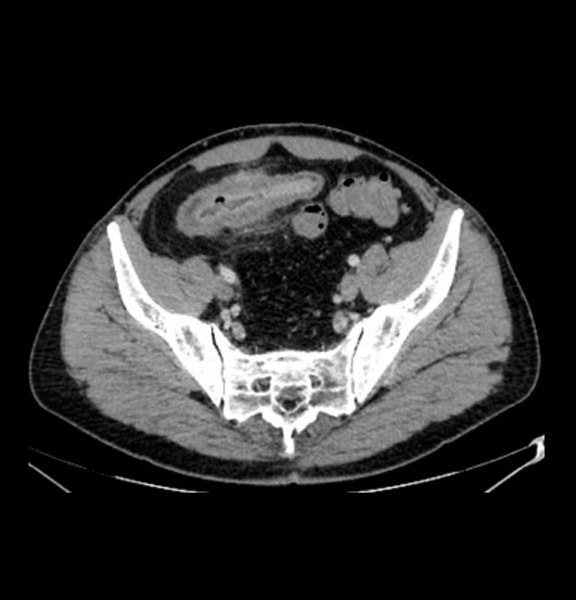

Iléite terminale avec hyperhémie muqueuse, épaississement des parois iléales, diminution de la lumière iléale et infiltration de la graisse adjacente.